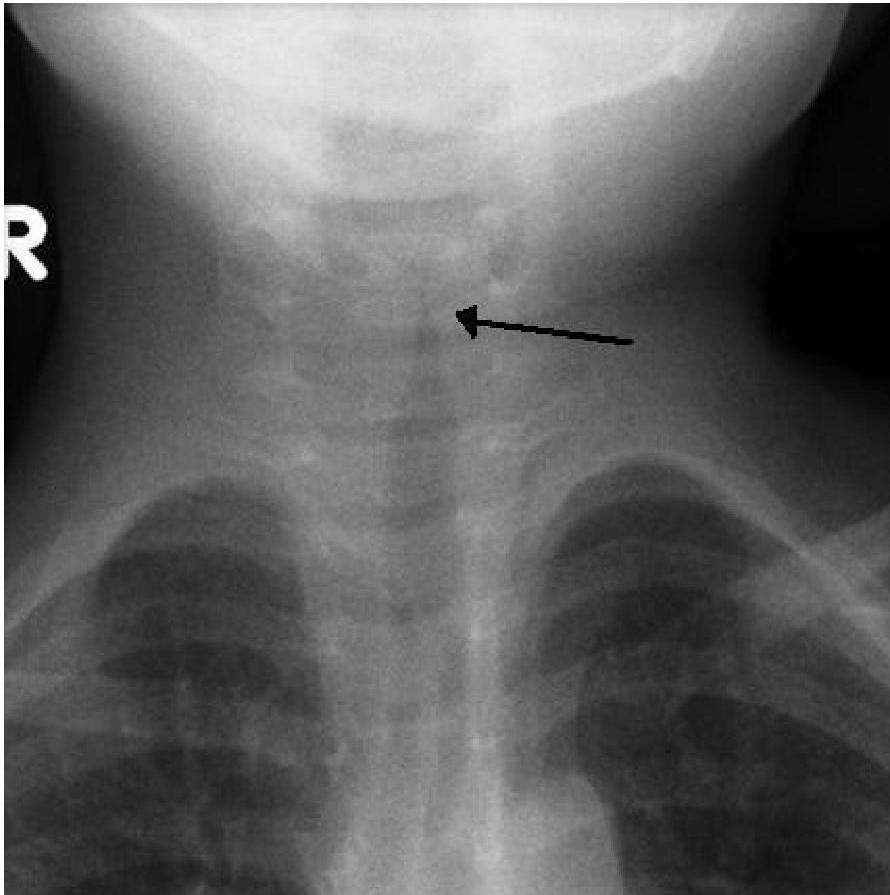

- The “Steeple Sign”: Characteristic subglottic narrowing seen on X-ray.

- X-ray, steeple sign